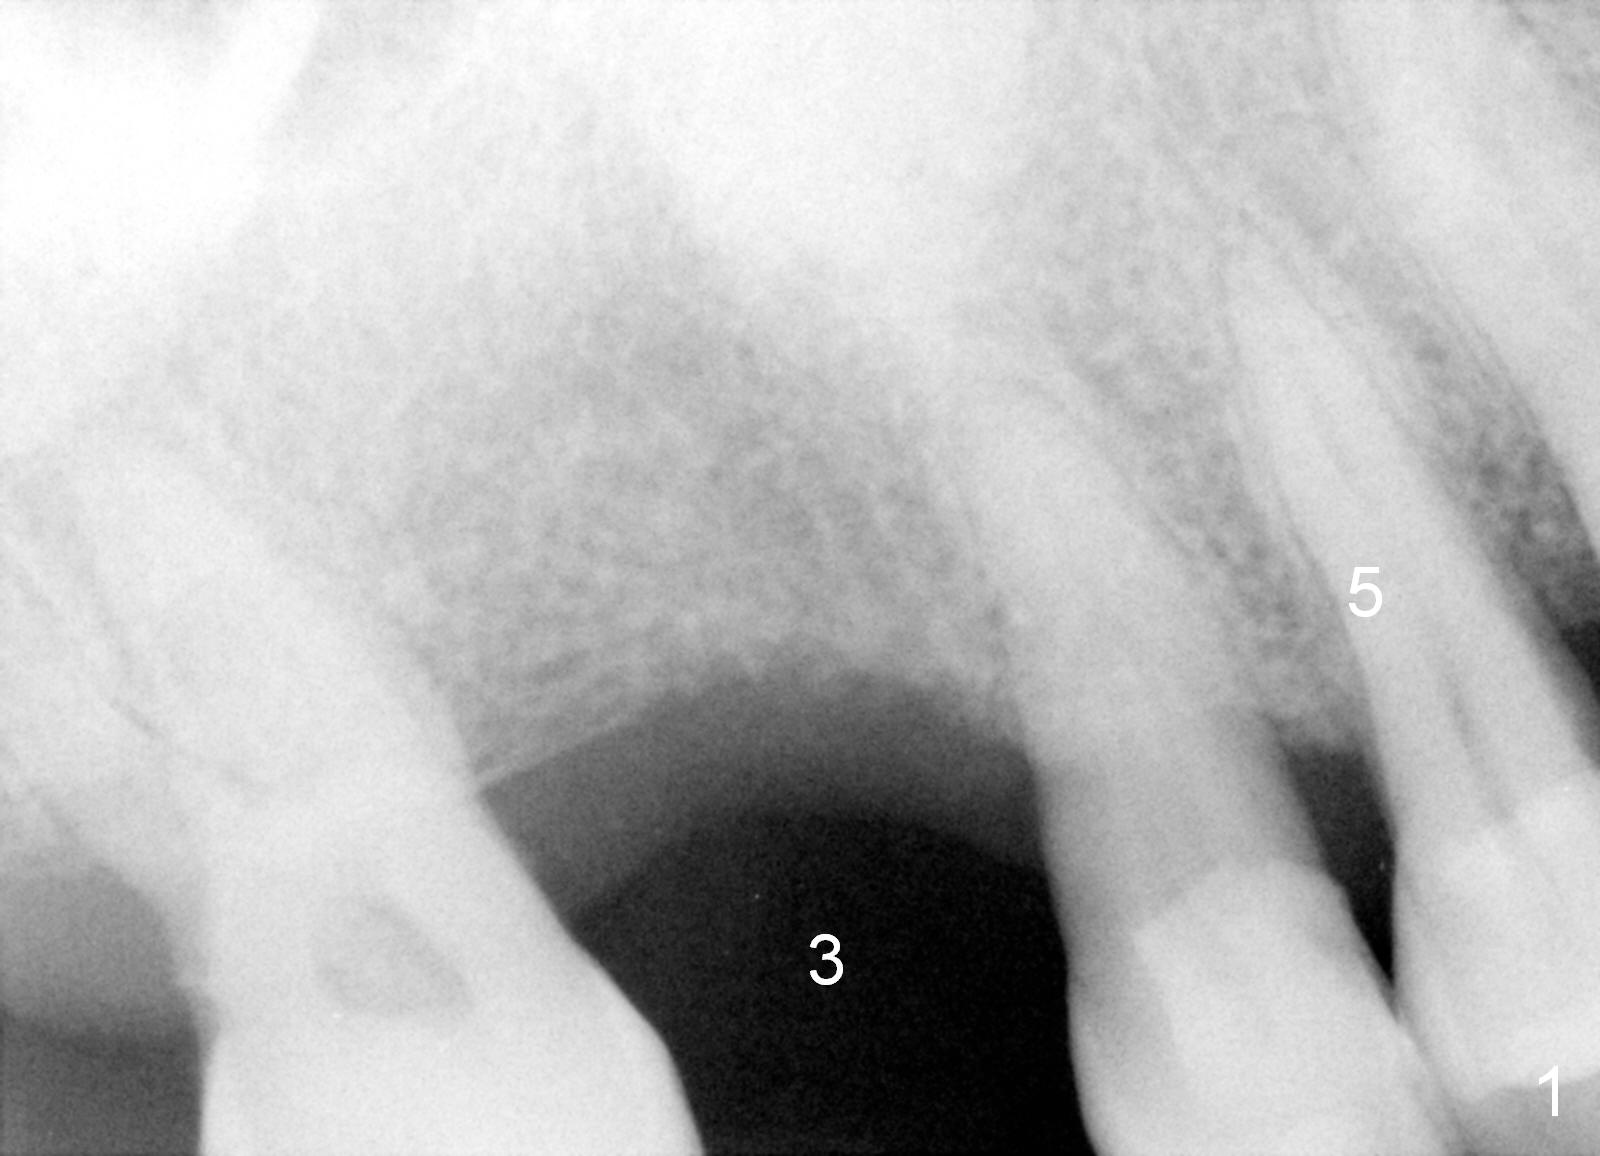

A 63-year-old man has lost the tooth #3 for long time: the first PA taken in our office is 5 years ago (Fig.1) before the tooth #5 received root canal therapy (Fig.2). The mesiodistal space of the edentulous is narrow, 8 mm (Fig.1) as compared to 10-11 mm for normal space.